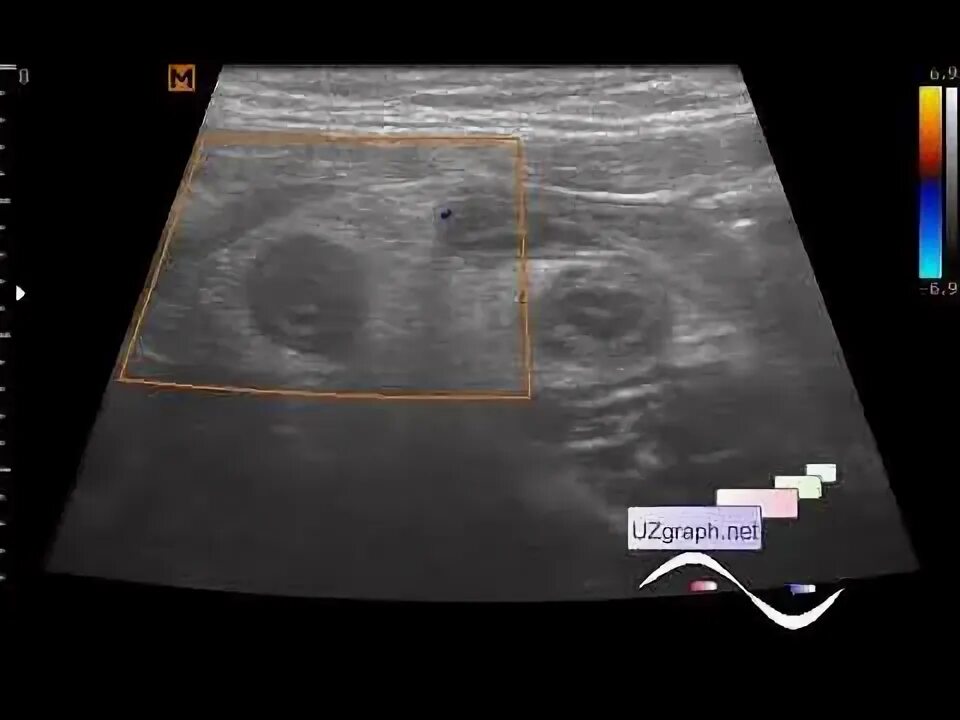

Какое узи при аппендиците